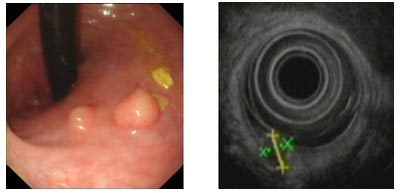

图三  直肠类癌